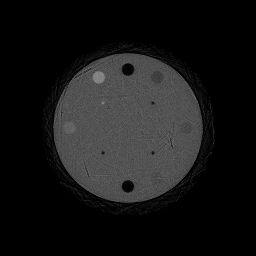

The RSP reconstruction accuracy (also referred to as density resolution) has been evaluated with the CTP404 phantom [53]. It is designed to measure how accurately a material property is reconstructed in a homogeneous region of the phantom. The CTP404 phantom is a 150 mm diameter epoxy cylinder, which contains 8 different material inserts with a diameter of 12.2 mm.

3.5 Evaluation of the CTP404 Phantom

In order to robustly determine the average RSP of the inserts on the reconstructed images, yet an another automatized algorithm has been implemented as the following:

-

(i)

At given reconstruction resolution (determined by the mm/pixel values), the exact center position of each insert is determined on the ground truth image (which has perfect contrast, zero noise and blurring).

(ii)

On the reconstructed CTP404 images, the mean RSP around the previously determined center positions was calculated—see Figure 7 as an illustration for the ground truth and ideal reconstructions, where the colored sections indicate the reconstructed RSP values of the inserts.

The extracted RSP values can be compared to the ground truth RSP values, as it was presented in details by [4].

The result of the reconstructed images of the CTP404 and CTP528 phantoms are shown in Figure 8, on the top and bottom rows respectively. The left-hand side column of Figure 8 presents the idealized case, while the middle and right-hand side columns show the more realistic silicon pixel and silicon strip detector models, respectively.

To quantify the quality of the reconstructed images, the RSP accuracy and its relative difference is shown in Figure 9(a), while Figure 9(b) shows the spatial resolution (as defined in Subsection 3.4). The reconstructed RSP values and their errors are summarized in Table 2.

The average relative RSP difference for the listed materials was found to be -0.66% for the ideal, -2.25% for the silicon pixel, and -2.64% for the silicon strip setups after processing 43 million protons. This average accuracy exceeds the required 1% uncertainty for the ideal setup [43].